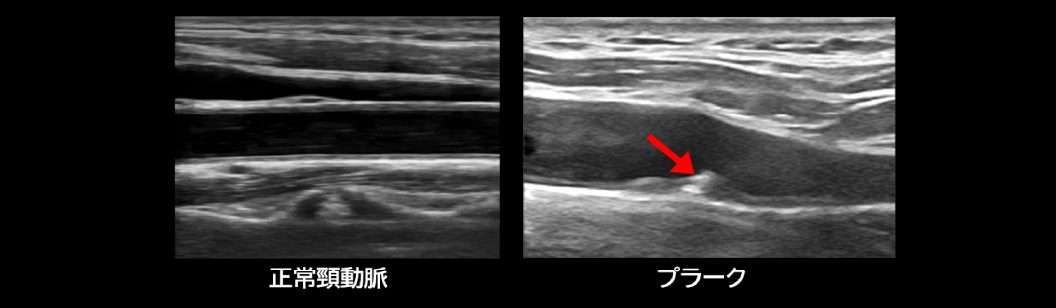

頸動脈超音波検査とは、超音波を頸部動脈に当てて、その反射を映像化することで頸動脈の状態を観察します。具体的には、動脈硬化によって厚くなった血管壁やこびりついたプラーク(脂肪などの線維)を確認することができます。

頸動脈超音波はそんな危険な動脈硬化を調べる検査です。